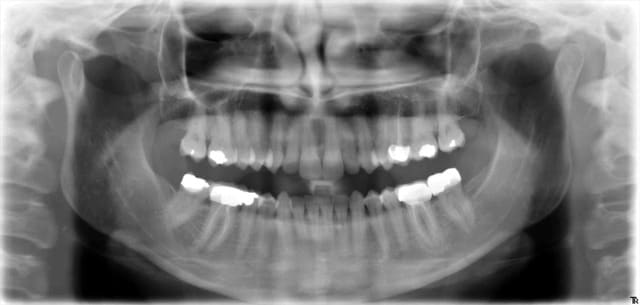

Sur la radio de Hokusai on voit combien de secteurs

18-17-16

17-16-15

16-15-14

3 secteurs DISTINCTS😀😀😀😀😀

Ici on peut voir 4 secteurs distincts de 3 dents contigues en rétro-coronaires aussi pourquoi pas.

18, 17, 16 - 16, 15, 14

48, 47, 46- 46, 45, 44

Je mets la définition de distinct pour que ca soit clair. Ces secteurs ne se confondent pas. -)

C'est pratique ces libellés plus on creuse et moins c'est clair. -)

Ici tu ne peux coter que 2 secteurs de 1 a 3 dents contigues dents contigues. radio centrée sur 46 et 16 donc 2 secteurs distincts.

47,46,45 et 17,16, 15.

Secteur 18-17-16

Secteur 17-16-15

Secteur 16-15-14

Sinon 2 secteurs

16-15-14 si on ne cherche pas le cdc